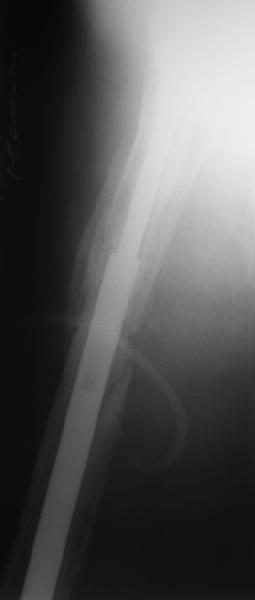

Female, rheumatoid, THA in 2003, car accident in 2006, failed plating. Nailing in Oct 2007. The nail is solid with hollow proximal part where the stem is docked. Last images are in 1 year after

nailing.

Спасибо за обсуждение. После нескольких дней тракции аппаратом сделали. Попытка закрытой репозиции не удалась из-за смещения по ширине, мешали фрагменты цемента. После их удаления репозиция получилась. Еще убрали немного цемента с ножки по латерльной стороне, чтобы обнажить 40-50 мм ее дистальной части, для плотной посадки гвоздя. Дальнейшее введение гвоздя было несложным. Протез показался нам стабильным в проксимальной части как латерально, так и медиально. Картинки в приложении.

THX for the discussion. After few days of traction by ex-fix the surgery was performed. An attempt of closed nailing was unsuccesful because of fragment translation, which was blocked by cement fragments. After removal of broken cement pieces reduction was reached "automagically". Also some cement from lateral part was removed by

chisel to expose distal 40-50 mm of the stem to allow tight fit of the nail. Further fixation by the nail was pretty easy and straightforward. Images attached. The stem looked stable in its proximal part both laterally and medially. Comments/critics are welcome.